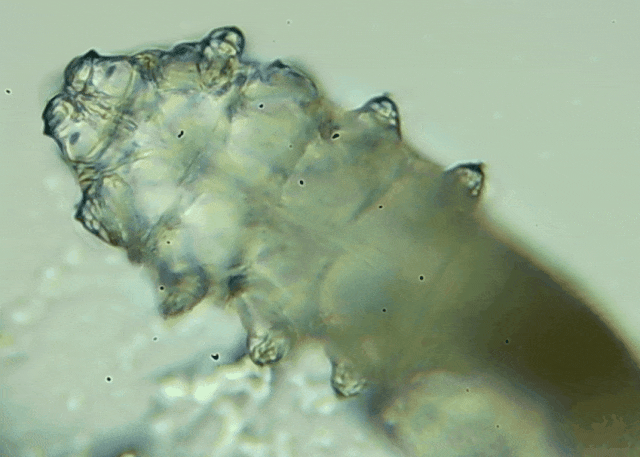

蠕形螨是一類肉眼看不見的寄生螨,常見的有毛囊蠕形螨和皮脂蠕形螨,常駐在人類的毛囊和皮脂腺里,尤其是眼睛的瞼板腺和睫毛根部。數(shù)量少時(shí),蠕形螨能與人體“和平共處”,但一旦你免疫力下降、油脂分泌旺盛或清潔不到位,他們就會(huì)以你難以想象的速度瘋狂繁殖。

當(dāng)螨蟲攻占眼部時(shí),通常會(huì)有這些癥狀,如反復(fù)發(fā)作的雙眼紅癢、干澀、燒灼感;分泌物增多,早起出現(xiàn)“眼屎拉絲”;睫毛容易掉,嚴(yán)重時(shí)出現(xiàn)倒睫或亂睫等;長(zhǎng)期螨蟲感染還會(huì)誘發(fā)干眼、角膜炎,甚至視物模糊等。